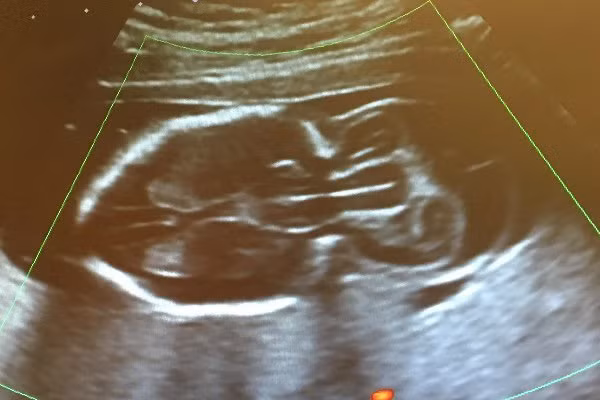

Cô con gái 6 tuần tuổi May Rose của cô Analee Gibney bẩm sinh đã bị thoát vị não – tức não phát triển thành một túi phía sau đầu thay vì bên trong vỏ não.

Khám thai lúc 20 tuần thì bác sĩ đã phát hiện ra điều này khiến giấc mơ của Analee bị vỡ vụn. Cô chẳng còn thiết tha làm những việc mà bà mẹ mang thai lần đầu nào cũng hứng thú như mua nôi, xe đẩy, quần áo trẻ sơ sinh.